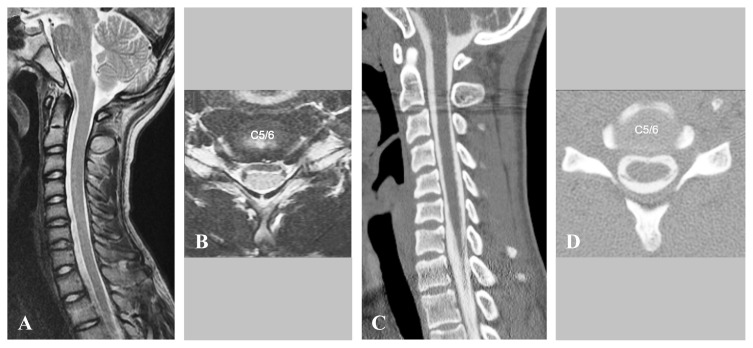

Hirayama disease, a form of cervical myelopathy predominantly affecting young males, is characterized primarily by distal muscle atrophy in the upper limbs. We investigated the surgical outcomes of duraplasty with laminoplasty for Hirayama disease. Five male patients with an average age of 17.4 years with Hirayama disease who had preoperative muscle atrophy and numbness in the upper extremities underwent duraplasty with laminoplasty. The severity of disability in activities of daily living was classified using the Tokumaru classification. Following cervical duraplasty with laminoplasty, all patients experienced significantly improved upper extremity performance. Hirayama disease is characterized by an inelastic dura that constricts and compresses the cervical spinal cord when the neck is flexed. Duraplasty with laminoplasty is proposed as an effective treatment for Hirayama disease.